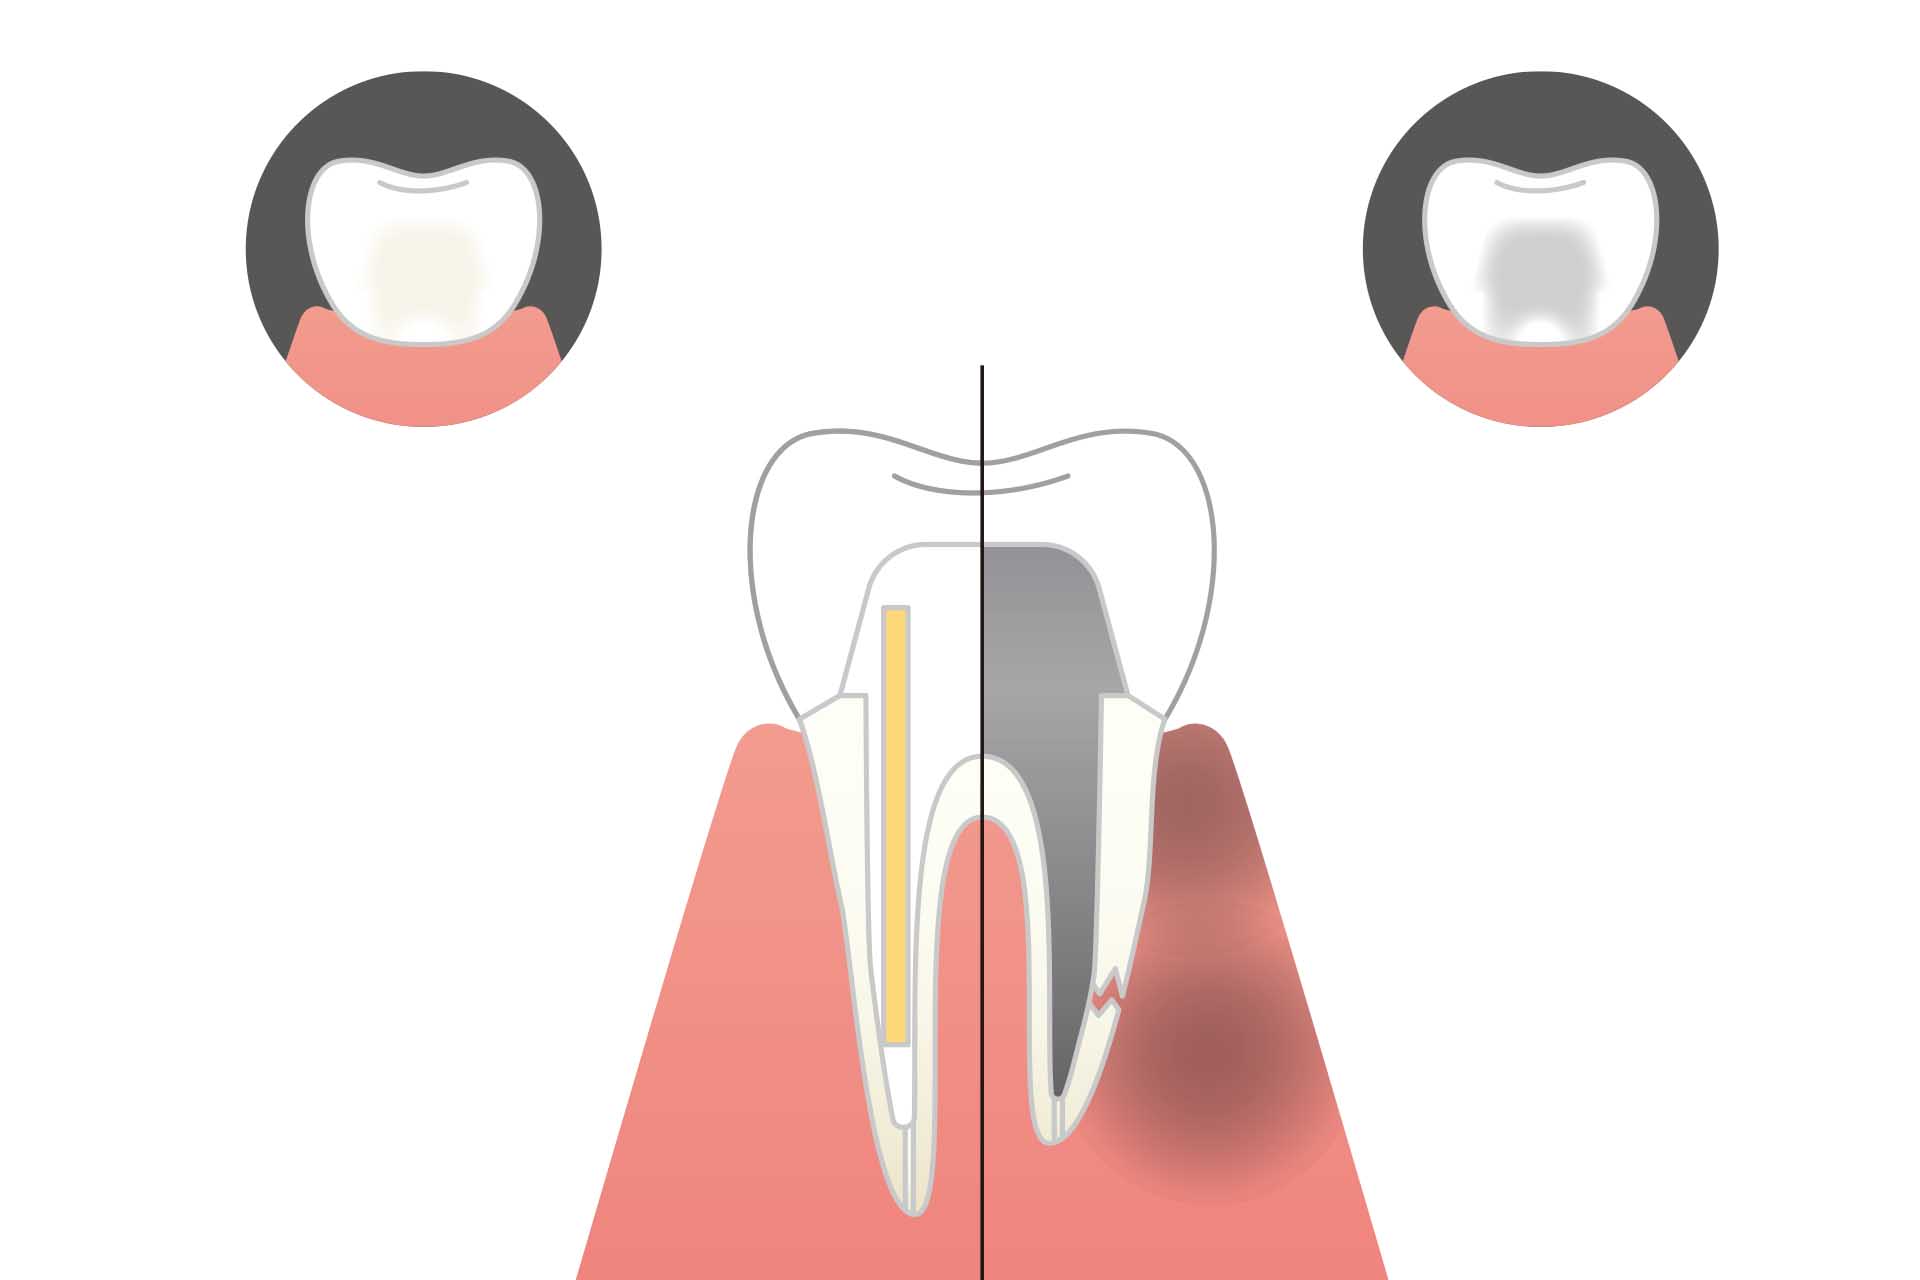

- Q 「抜歯してインプラント」と言われましたが、本当に残せませんか?

- A多くのケースで、精密な根管治療や外科的アプローチ(歯根端切除術など)を組み合わせることで、歯を残せる可能性があります。 ただし、歯の根が真っ二つに割れている(歯根破折)場合などは、無理に残すと周囲の骨まで壊してしまうため、抜歯が最善の選択となることもあります。当院ではマイクロスコープで「残せるかどうかの診断」を精密に行いますので、まずはセカンドオピニオンとしてご相談ください。

- A精密な根管治療を行い、その上に適合の良い被せ物(セラミック等)を装着すれば、10年、20年と使い続けることが可能です。ただし、根管治療をした歯は「神経がない=栄養が届かない」状態のため、健康な歯よりも脆くなっています。 長持ちさせるためには、当院で行う定期的なメンテナンス(噛み合わせのチェックなど)が非常に重要です。

MTAセメント

〜生体となじみ、細菌を寄せ付けない封鎖材〜

根の中を綺麗にした後、最後に隙間なく詰め物(充填)をすることが重要です。

当院では、世界的に高く評価されているMTAセメントを使用します。

MTAは強アルカリ性で高い殺菌力を持ち、水分があっても膨張しながら固まるという特殊な性質を持っています。

これにより、根の先端をミリ単位の狂いもなく密閉(封鎖)し、将来的な細菌の再侵入を鉄壁のガードで防ぎます。

ファイバーコア

〜歯の「しなり」を再現し、根の破折を防ぐ〜

根管治療を終えた歯は、いわば「枯れ木」のような状態。そのままでは割れやすいため、しっかりとした土台(コア)が必要です。

従来の金属の土台(メタルコア)は硬すぎて、噛む力がかかった時に「楔(くさび)」のように働いて歯の根を割ってしまうことがありました。

当院では、歯に近い弾性を持つファイバーグラスの芯(ファイバーコア)を使用。

衝撃を吸収し、歯を根元から守ります。